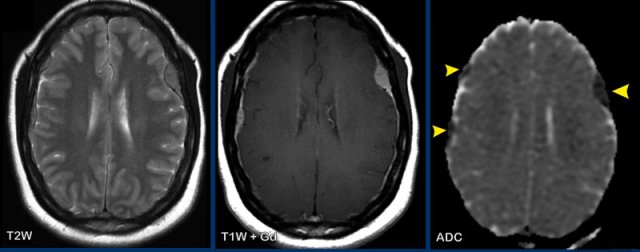

These images are of a 76-year old woman, who was confused after a fall.

First look at the images and then continue reading.

Question:

- What is the most likely diagnosis?

- Which findings are typical for this diagnosis?

The findings are:

- Hyperdense lesion on the NECT with some vasogenic edema.

- MR shows multiple lesions with solid enhancement and diffusion restriction.

- On T2W the lesions show a low signal intensity

- One lesion is located in the corpus callosum and another one is periventricular.

All these findings are typical for a primary CNS lymphoma, which is different from a systemic lymphoma.

These tumors make up for 6-7% of all CNS tumors and the histology is a B-cel NHL.

They are mostly located periventricular subependymal, in the corpus callosum and in the basal ganglia.

Always think lymphoma in a solid enhancing lesion which is located near the ventricles.

The hyperdense appearance on CT and the slight hypointensity on T2W-imaging, as well as the restricted diffusion are attributed to the dense cellularity of the lymphomatous tissue.

In immuno-compromised patients the enhancement can be ring-like.

This patient has a lot of edema, but in many cases the edema is very limited.